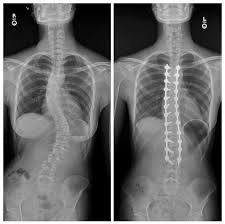

• Escoliosis;

Si bien, la fusión eliminará parte de la flexibilidad espinal, la mayoría de las fusiones espinales solo incluyen pequeños segmentos de la columna vertebral y no limitarán en gran medida el movimiento. De hecho, la mayoría de los pacientes nunca notarán una disminución del rango de movimiento.